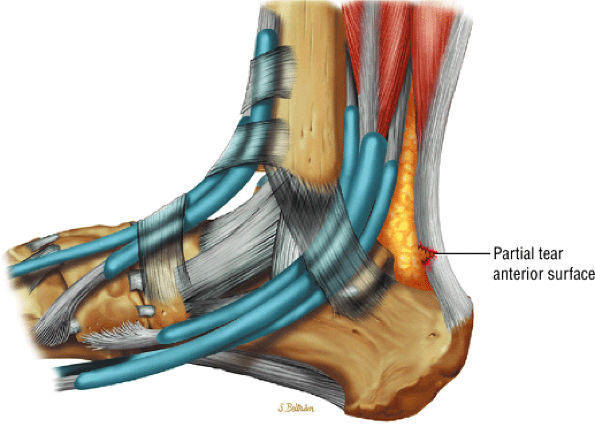

FIGURE 5.120 ● Anterior surface partial tear of the Achilles tendon on a lateral color graphic.

FIGURE 5.121 ● (A) Posterior surface partial tear of the Achilles tendon proximal to the os calcis. Lateral color lateral illustration. Sagittal (B) and coronal (C) FS PD FSE images of a partial tear of the Achilles tendon. The coronal plane image (C) is useful in demonstrating medial tendon fiber disruption.